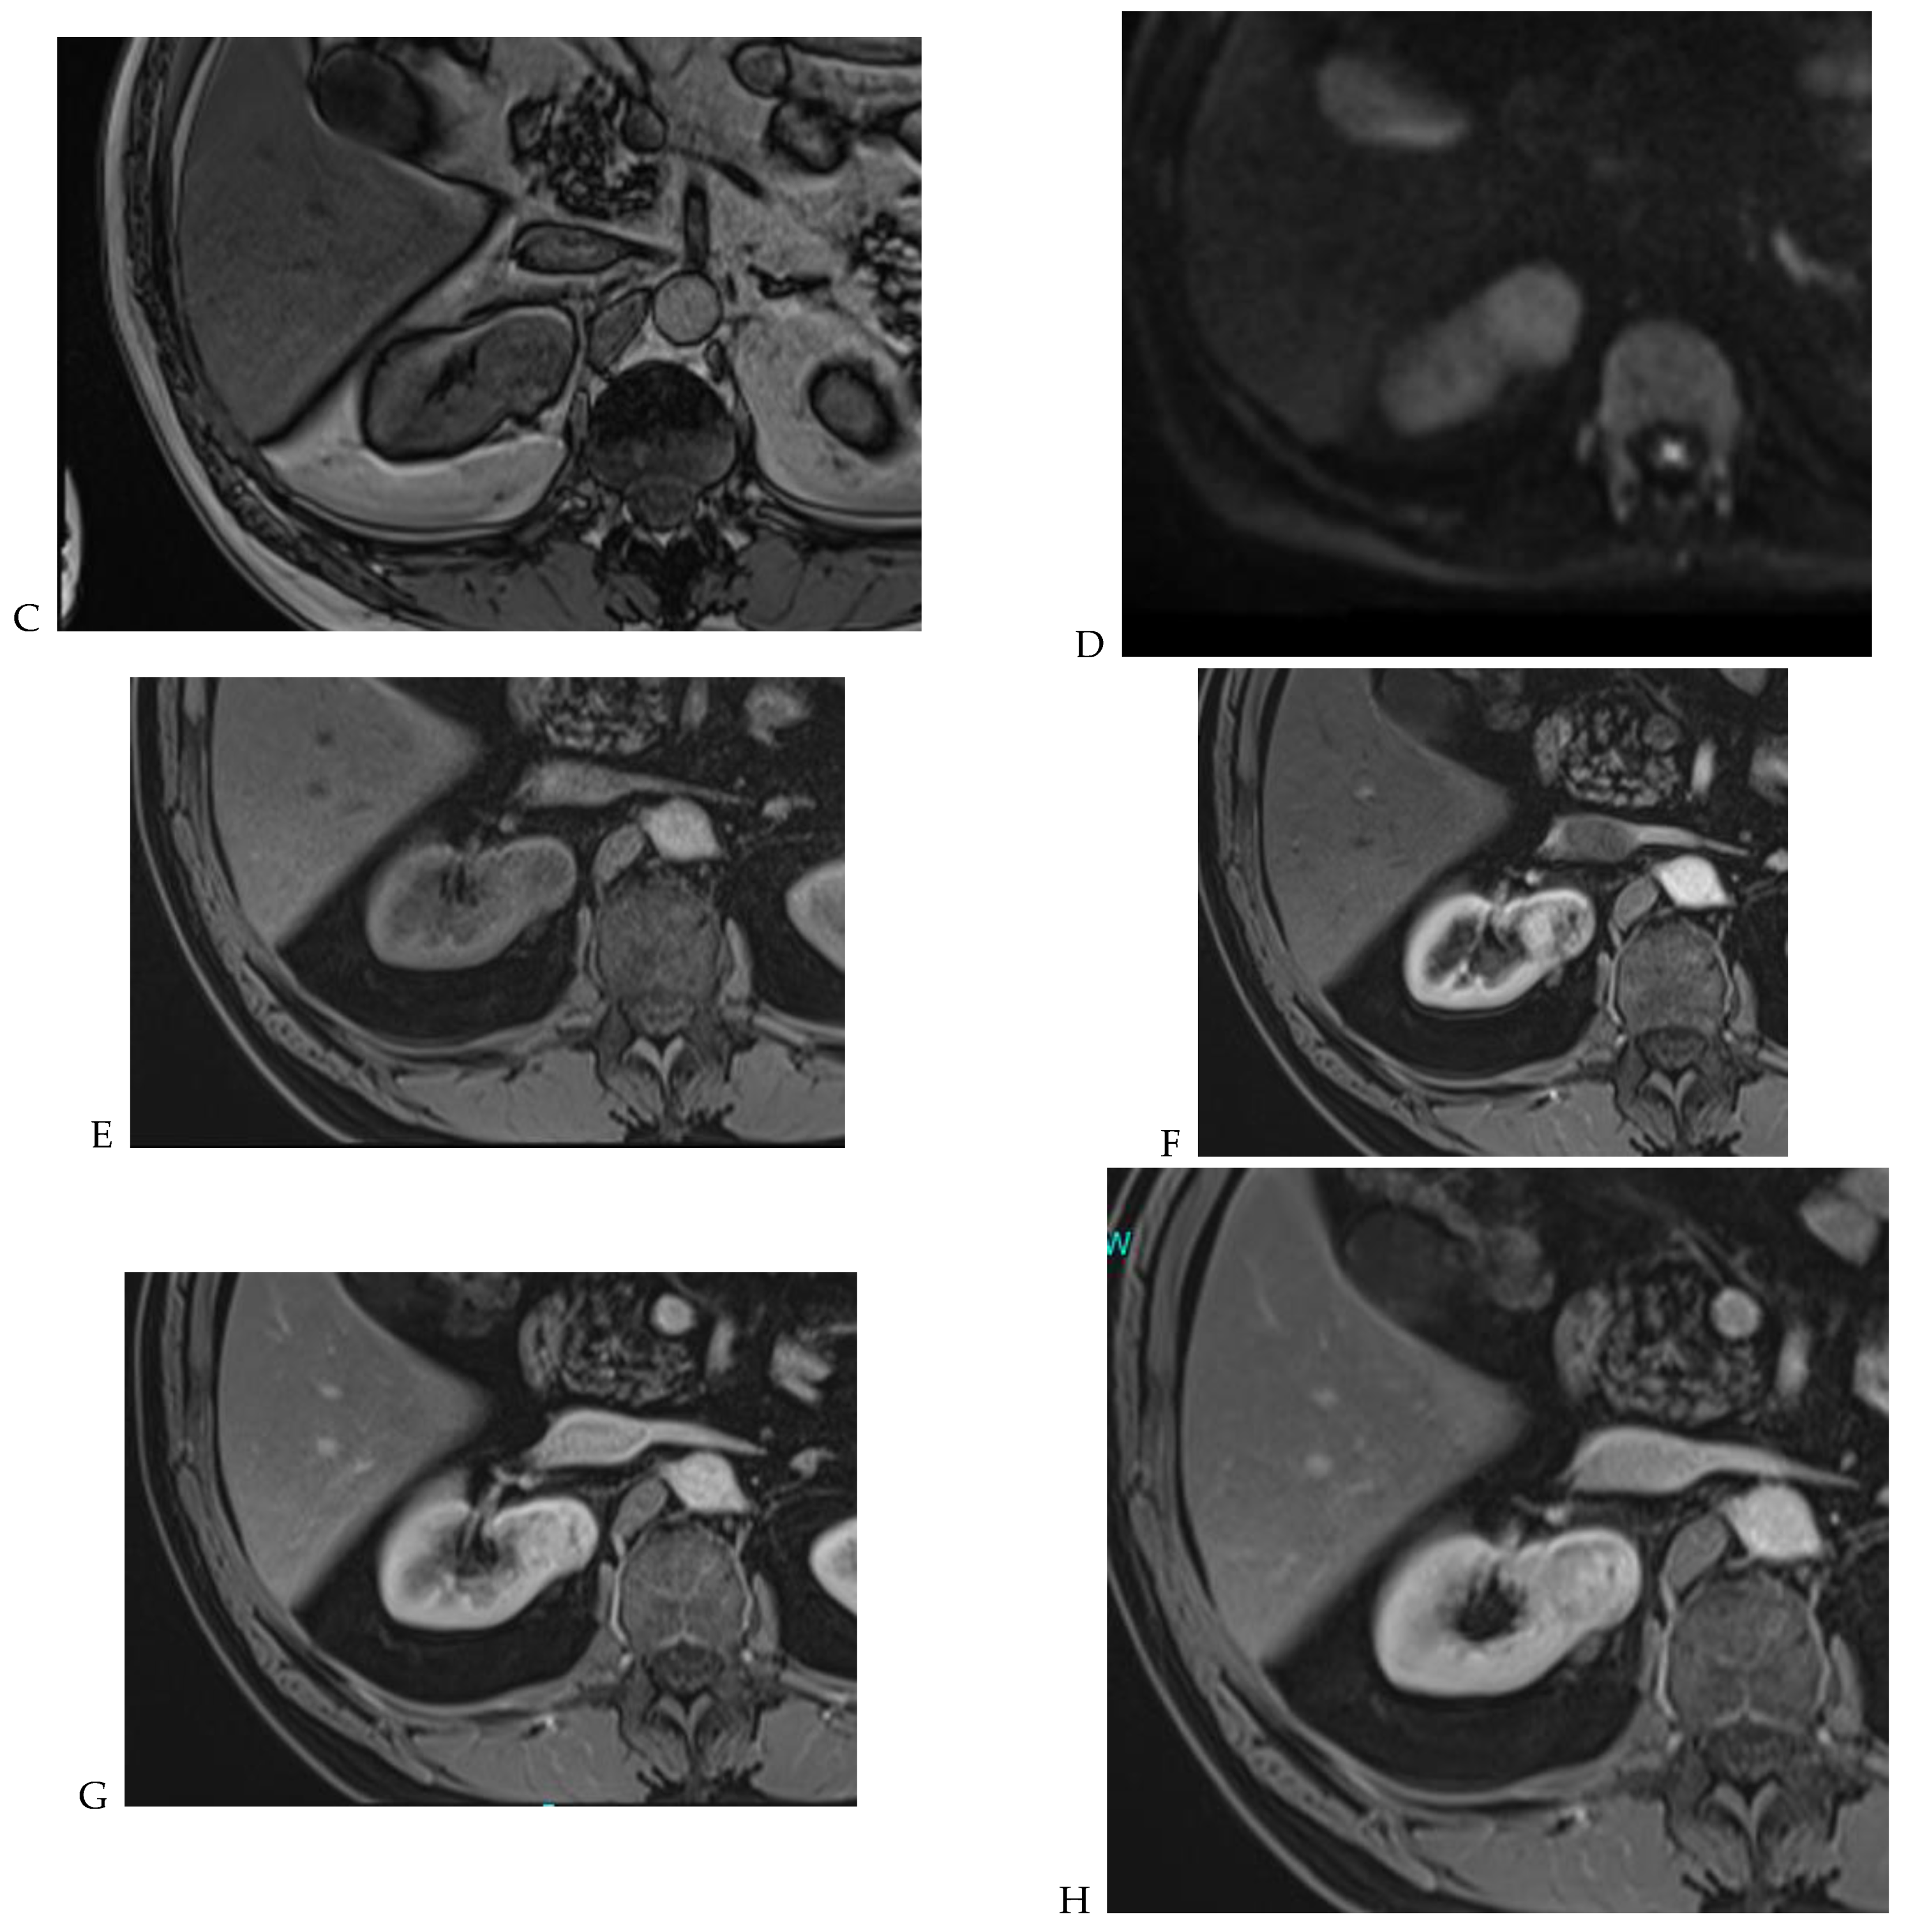

Figure 7.

Papillary renal cell carcinoma in the right kidney of a 75-year-old-woman. (A) Axial T2-weighted fast SE image shows a homogeneous 1.8 cm mass in the posterolateral region of the right kidney, with a lower SI compared to renal parenchyma. Transverse in-phase (B,C) opposed-phase MR images do not show a significant signal loss on the opposed-phase image. (D) The ADC map shows restriction of tumor diffusion into the renal mass. Transverse nonenhanced (E) and gadolinium-enhanced T1-weighted gradient-echo spoiled MR images in (F) corticomedullary, (G) nephrographic, (H) and delayed phase images show progressive enhancement without washout; the mass is hypovascular compared to the renal cortex.

The detection of macroscopic fat in a renal mass is essential because, in the absence of calcification, it is almost always characteristic of a classic (fat-rich) angiomyolipoma, the most common solid benign renal mass. The macroscopic fat component shows a loss of signal intensity on T1-weighted fat-suppressed images. Angiomyolipomas are also characterized by the presence of an India ink artifact on opposed-phase T1-weighted images at the junction of the mass and normal renal parenchyma, indicating a fat–water interface. T1-weighted gradient-echo inversion recovery imaging allows the detection of microscopic/intracytoplasmic fat. Microscopic intracellular fat is present in clear cell RCC (Figure 5), resulting in a signal drop on opposed-phase images. A signal drop has also been described in angiomyolipomas, including fat-poor angiomyolipomas (Figure 6). Gadolinium-enhanced T1-weighted three-dimensional fat-suppressed gradient-echo imaging is useful to assess the enhancement pattern in a renal mass. It allows the differentiation of hypervascular masses from hypovascular lesions with late and slow enhancement as seen in papillary RCC (Figure 7). T2-weighted sequences are essential for differentiating cystic renal masses from solid renal masses. The T2 signal intensity of a solid renal mass is also helpful in suggesting certain histologic subtypes of RCC. Both fat-poor angiomyolipomas (Figure 6) and papillary RCCs (Figure 7) have a low signal intensity on T2-weighted images, whereas other renal masses have an intermediate or high signal intensity. Several studies have suggested the potential utility of apparent diffusion coefficient (ADC) values to further characterize a renal mass [38]. Both fatty angiomyolipomas and papillary RCCs have low ADC values.